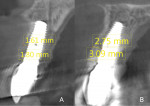

Labial plate dimension (LPD): Measurements in millimeters (mm) were taken at two levels, L1 and L2, as previously described by Chu et al (Figure 8).19 L1 corresponded to the implant-abutment interface (IAI) equivalent to the midfacial labial plate bone crest; L2 matched the implant body roughly 5 mm from the IAI and bone crest coinciding with the upper portion of the INV implant transition zone where the diameter and shape shifts from a tapered to cylindrical form, roughly 40% the implant length. At each level, two reference points were identified: (1) the outermost aspect of labial bone plate, and (2) the first radiographic bone-to-implant contact point connected by a straight line perpendicular to the implant body. The distance between the two points at each level was measured (mm) using bundled CBCT digital imaging software (i-Dixel), and the bone plate thickness was recorded 1 year post-surgery (Figure 8).

LPD: Mean labial plate thickness was 1.18 ± 0.16 and 2.84 ± 0.16 mm at L1; 0.79 ± 0.14 and 2.56 ± 0.20 mm at L2 for T and INV groups, respectively.

The results of this retrospective comparative study demonstrate that there are statistically significant differences between the labial bone plate thickness of T versus INV implants measured at L1 and L2. The mean difference in millimeters between the groups was 1.66 (L1) and 1.77 (L2), which was more than double that of the T group. In addition, 19% of implants in the T group had no visible labial plate on CBCT at follow-up, while all INV implants had an observable labial plate. The clinical relevance is that INV implants had a thicker labial plate, more than 2 mm, which may enable more sustainability over time to maintain biologic and esthetic results. It is significant that the amount of the platform switch on the INV implants was greater than that on the T implants. Studies have shown that platform switching plays a significant role in marginal bone preservation; therefore, only platform-switched implants were included in the T group.43-45 However, INV possessed a different platform-switched design called "variable" platform switching (VPS) (Figure 7). By physically shifting the abutment-implant junction further from the platform, more horizontal space was available for biologic width formation. Combining dual-zone bone grafting over the platform of the implant with this VPS design conceptually encourages more bone and maintenance for soft tissue support.